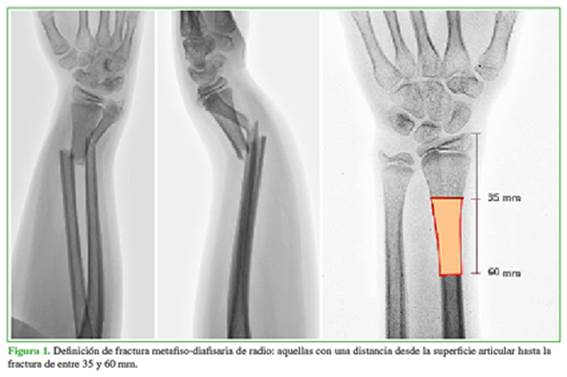

Se llevó a cabo un estudio comparativo que fue aprobado por el Comité de Ética de nuestra institución. Se incluyó a 36 pacientes de entre 10 y 16 años de edad con fracturas metafiso-diafisarias cerradas de radio distal quienes fueron sometidos a reducción cerrada y FPC (grupo A, n = 17) o EEE (grupo B, n = 19) en un período de seis años (2012-2018). Se definió a las fracturas metafiso-diafisarias como aquellas que presentaban una distancia desde la fractura hasta la superficie articular de entre 35 y 60 mm (Figura 1).10